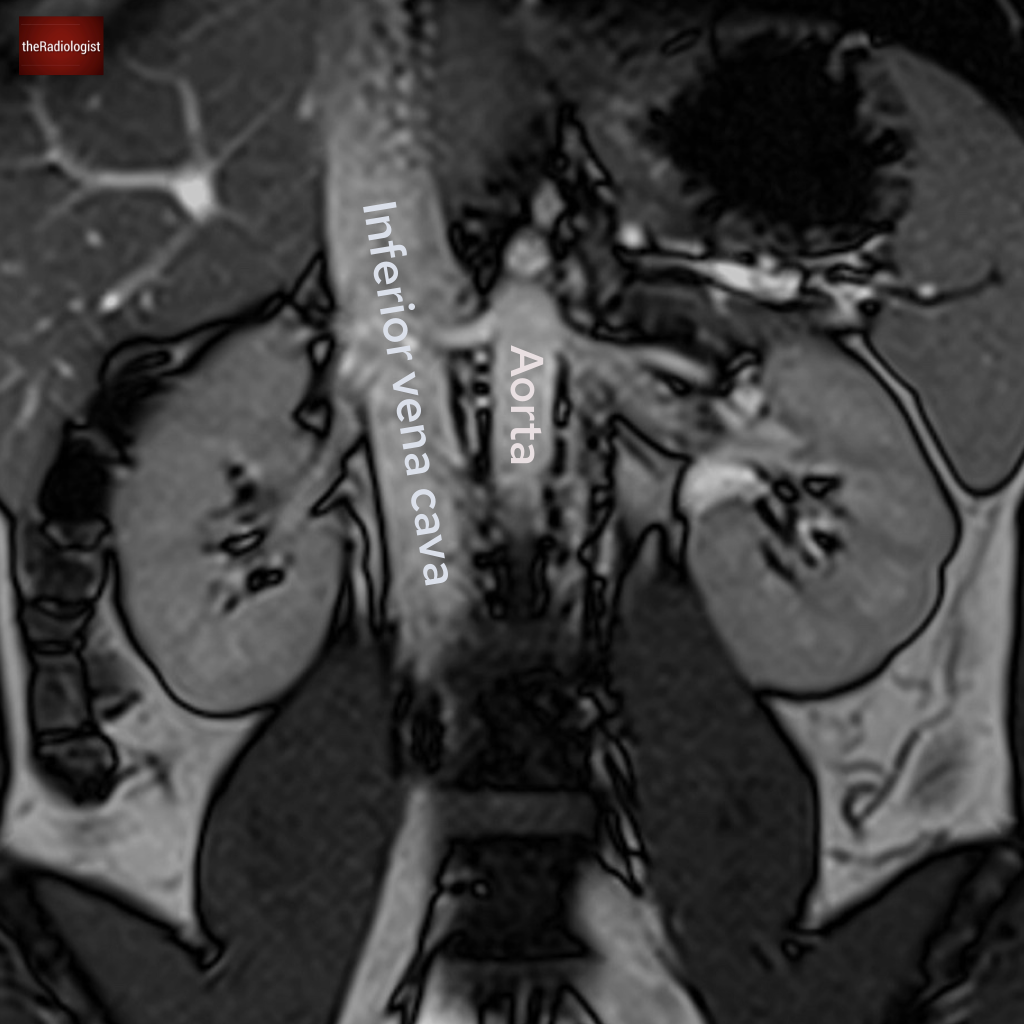

Case 4

Another abdominal MRI in this case. What is the arrow pointing at?

Choose one from the following options: